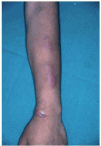

El periodo de incubación oscila entre 3 semanas y 6 meses111. La principal presentación cutánea es la forma diseminada con 5-100 nódulos eritematosos circunscritos o con tendencia a confluir en grandes masas con fístulas de drenaje múltiples100 (figs. 15A y B y 16). También se puede presentar como nódulos subcutáneos simulando lesiones vasculíticas128. Se suelen localizar en las regiones dorsales de las extremidades100. Preferentemente afectan las extremidades inferiores129 y deberían entrar en el diagnóstico diferencial de los procesos que cursan con nódulos crónicos en dicha localización119 (fig. 17). No suelen tener disposición lineal ni esporotricoide. Las lesiones de mayor tamaño pueden ser dolorosas y son raros los síntomas sistémicos. En excepcionales ocasiones puede precederse de afectación pulmonar130 o de fiebre periódica131. La segunda forma de presentación, en orden de frecuencia, son las celulitis localizadas, los abscesos subcutáneos o la osteomielitis. La tercera forma es la relacionada con el uso de catéteres100.

Figs. 15A y B.--Nódulos por M. chelonae en extremidades inferiores.

Fig. 16.--Detalle de la anterior.

Fig. 17.--Lesiones en extremidades inferiores por M. chelonae.